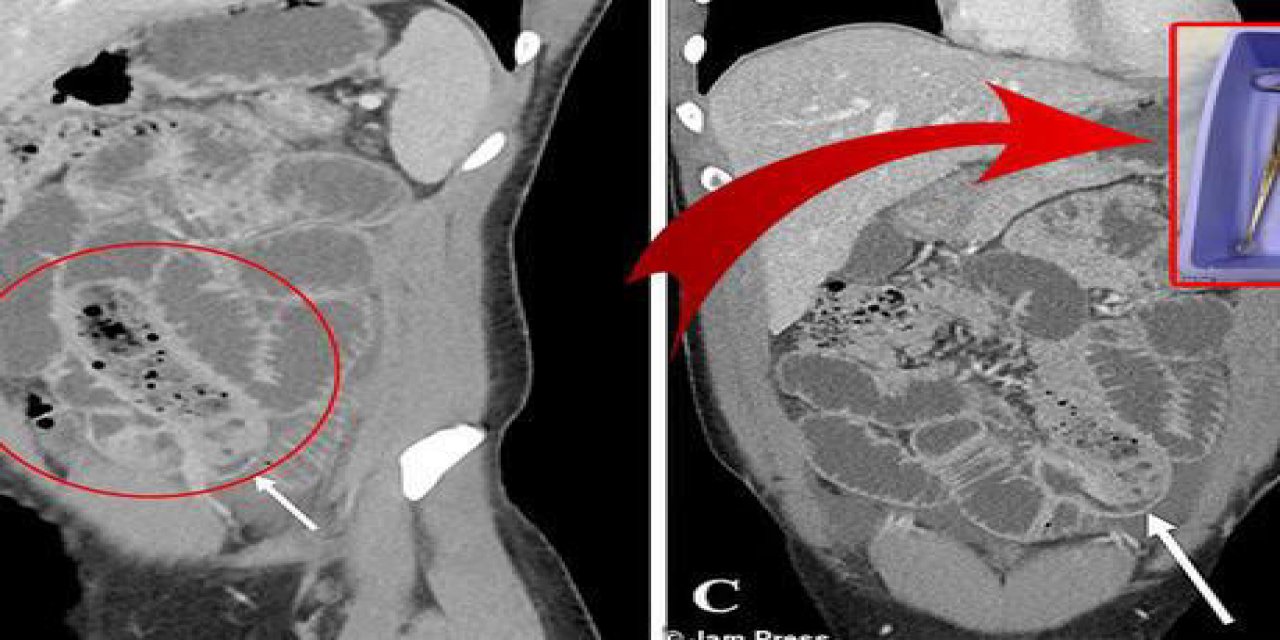

Daha sonra yapılan detaylı tetkikler sonucunda ilginç olay gün yüzüne çıktı. Söz konusu adamın ince bağırsağında kondoma sarılmış bir muz bulundu. Durumu gören doktorlar gözlerine inanamadı.

Röntgen çekilmesinin ardından hasta, apar topar ameliyata alındı. Doktorlar ameliyatın başarılı geçtiğini ve kondomla sarılmış muzun şahsın vücudundan çıkarıldığını aktardı. Doktorlar, hastanın bir öfke nöbeti geçirdiğini ve muzu bu sırada yuttuğunu düşündüklerini de belirtti.

Ameliyatı gerçekleştiren doktorlar ise meslek hayatlarında ilk defa böyle bir vakayla karşılaştıklarını söyledi. Benzer durumların uyuşturucu kaçakçılarında görüldüğünü belirten doktorlar yine de bu durumun nadir olduğunu bir kez daha hatırlattı.

ABD’nin önde gelen tıp dergilerinden olan Cureus da yaşanan olayı sayfalarına taşıdı. Söz konusu dergi, yaşanan olayı detaylı bir şekilde anlatarak adamın bağırsaklarının 24 saattir çalışmadığını ve ölmeye çok yakın olduğunu aktardı.